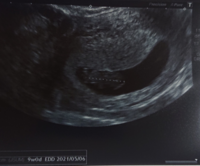

Jul 30, · 目次赤ちゃんの心拍はいつから確認できるの?赤ちゃん用心拍計やアプリで確認してもいいの?赤ちゃんの心拍数の目安心拍確認できない。その後の対応は?心拍確認後の流産の割合は?赤ちゃんの心拍停止「9週の壁」Apr 09, · 妊娠9週目(9w)に入り、ピークを迎えるつわりに苦しんでいるママも多いのではないでしょうか。安定期に向けてお腹の赤ちゃんもどんどん成長を続けています。そろそろ指や爪もできてくるころです。今回は、妊娠9週目に感じるママの身体の変化や赤ちゃんの様子、過ごし方についMar 13, · 妊娠してから出産まで、赤ちゃんの体は日々少しずつ変化していきます。ほんの1mmにも満たなかった受精卵が約3,000gの赤ちゃんに成長するまでの過程は、とても神秘的。 お腹の中で赤ちゃんがどのような成長経過をたどるのか、妊娠週数を追ってみていきましょう。

Mar 22, 17 · 妊娠9週目の「母親の体」と「赤ちゃん」の様子について解説します。母体における乳房や子宮の変化、赤ちゃんの発達状況について紹介するとともに、妊産婦の時期に必要なカルシウムの摂取方法についても紹介します。妊娠9週とは?妊娠9週目とは「妊娠63日Nov 10, · 「9週の壁」が怖かった:妊娠7w〜9w日記 なっているのも、手足がふいふい動いているのも、心拍も確認できたので安心しました。赤ちゃん239mm、心拍168bpmです。子育てママを応援する 「balloon 赤ちゃん保健室」, Kani 306 likes · 14 talking about this 岐阜県可児*美濃加茂市で開催しているベビーマッサージ教室です。アットホームな雰囲気のレッスンとお母さん達に人気!現役保健師によるレッスンです。

妊娠9週目エコー写真や胎児の大きさ平均 9週の壁 流産症状や原因 妊娠初期 All About